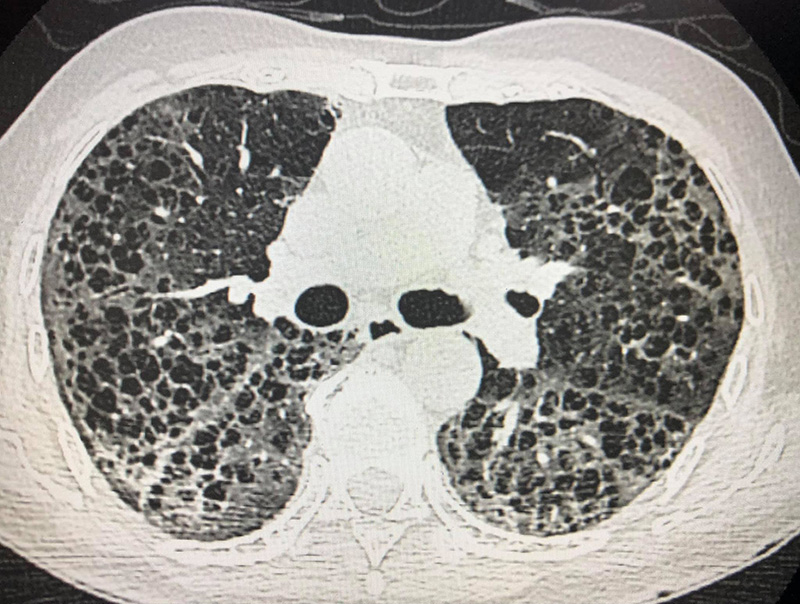

สำหรับเจ้าของปอดรายนี้ เป็นชายไทยวัย 80 ปี ไม่ดื่มเหล้า ไม่สูบบุหรี่ ติดเชื้อจากลูกหลานที่มาเยี่ยม เมื่อเอกซเรย์ปอดพบฝ้าขาว 2 ข้าง พอสแกนปอดพบเนื้อเยื่อปอดอักเสบรุนแรง มีทั้งฝ้าขาว รอยโรคเหมือนร่างแห และลักษณะผิดปกติคล้ายรังผึ้งกระจายทั่วไป